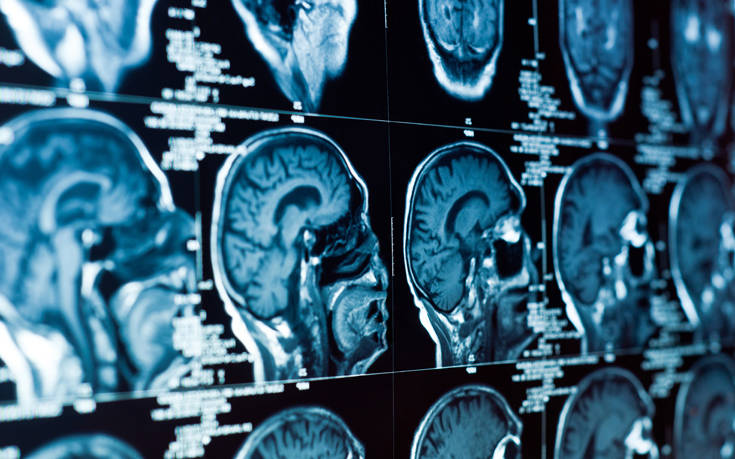

Οι ερευνητές του Πανεπιστημίου του Σάο Πάολο μίλησαν στο συνέδριο «Annual Meeting of the Radiological Society of North America» για τα ευρήματά τους, τις μαγνητικές τομογραφίες στους εγκεφάλους 59 υπέρβαρων και 61 φυσιολογικού βάρους εφήβων.

Η μελέτη, που περιμένει τη δημοσίευσή της, βρήκε πως οι υπέρβαροι έφηβοι εμφανίζουν βλάβες στο μεσολόβιο, την πυκνή δέσμη νευραξόνων που επιτρέπει την ανταλλαγή πληροφοριών μεταξύ των δύο ημισφαιρίων του εγκεφάλου. Αλλοιώσεις ανιχνεύτηκαν και σε άλλες εγκεφαλικές δομές.